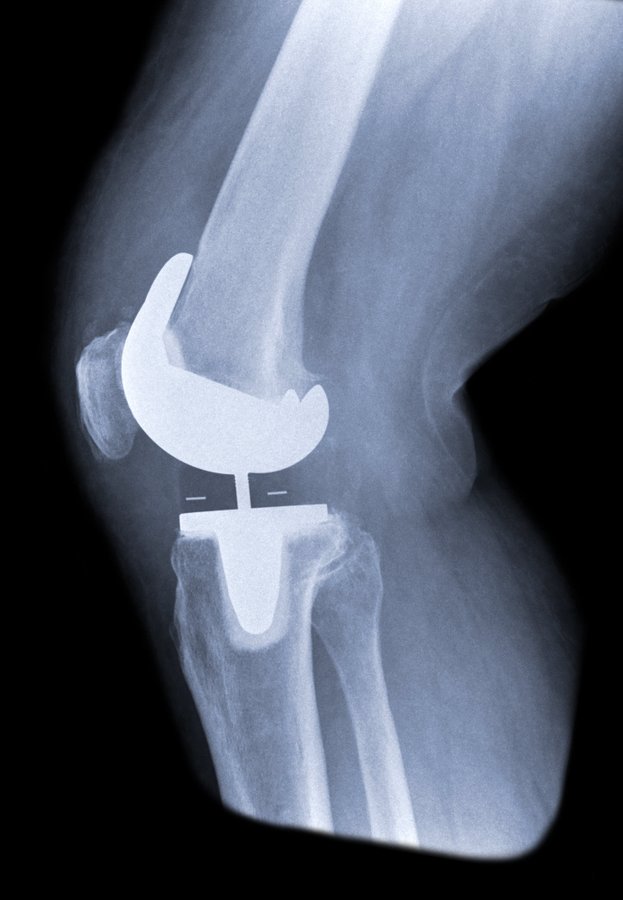

You’ve tried all the non-surgical methods, but it looks like you need a knee replacement. Here is a list of questions to ask your doctor before knee replacement surgery: ow.ly/DcBO30qxRFV